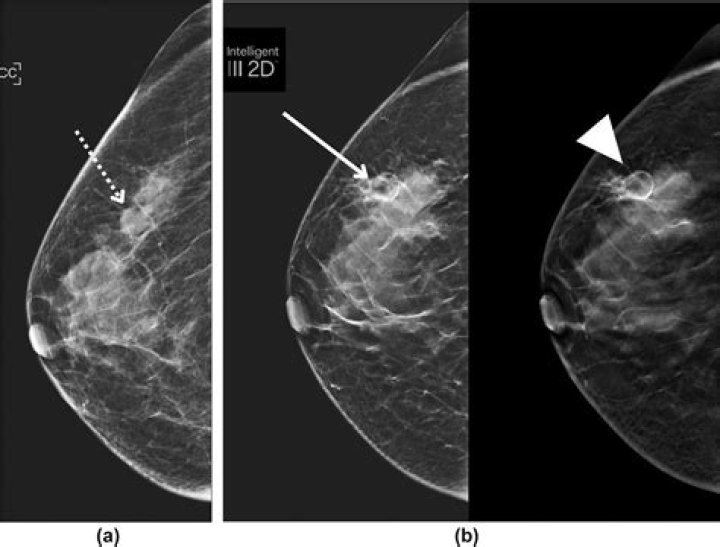

Can fat necrosis be seen on ultrasound?

Breast ultrasound Fat necrosis may be seen as a hypoechoic mass with well-defined margins +/- mural nodule(s). Ultrasound of fat necrosis should always be interpreted in the context of mammographic findings. Aspiration of an oil cyst shows typically a milky, emulsified fat appearance.

What does fat necrosis look like on ultrasound?

On sonography, the appearance of fat necrosis ranges from a solid hypoechoic mass with posterior acoustic shadowing to complex intracystic masses that evolve over time. Fat necrosis may appear as cystic or solid masses. Cystic lesions appear complex with mural nodules or internal echogenic bands.